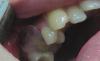

Alexey Doc Опубликовано 24 сентября, 2013 Поделиться Опубликовано 24 сентября, 2013 Фото конечно поганенькое, но суть по-моему понятна. Ссылка на комментарий

АнтонТЛТ Опубликовано 24 сентября, 2013 Поделиться Опубликовано 24 сентября, 2013 Фото конечно поганенькое, но суть по-моему понятна. Алексей, можно подробнее как делаешь из системы?Лучше с фотками 1 Ссылка на комментарий